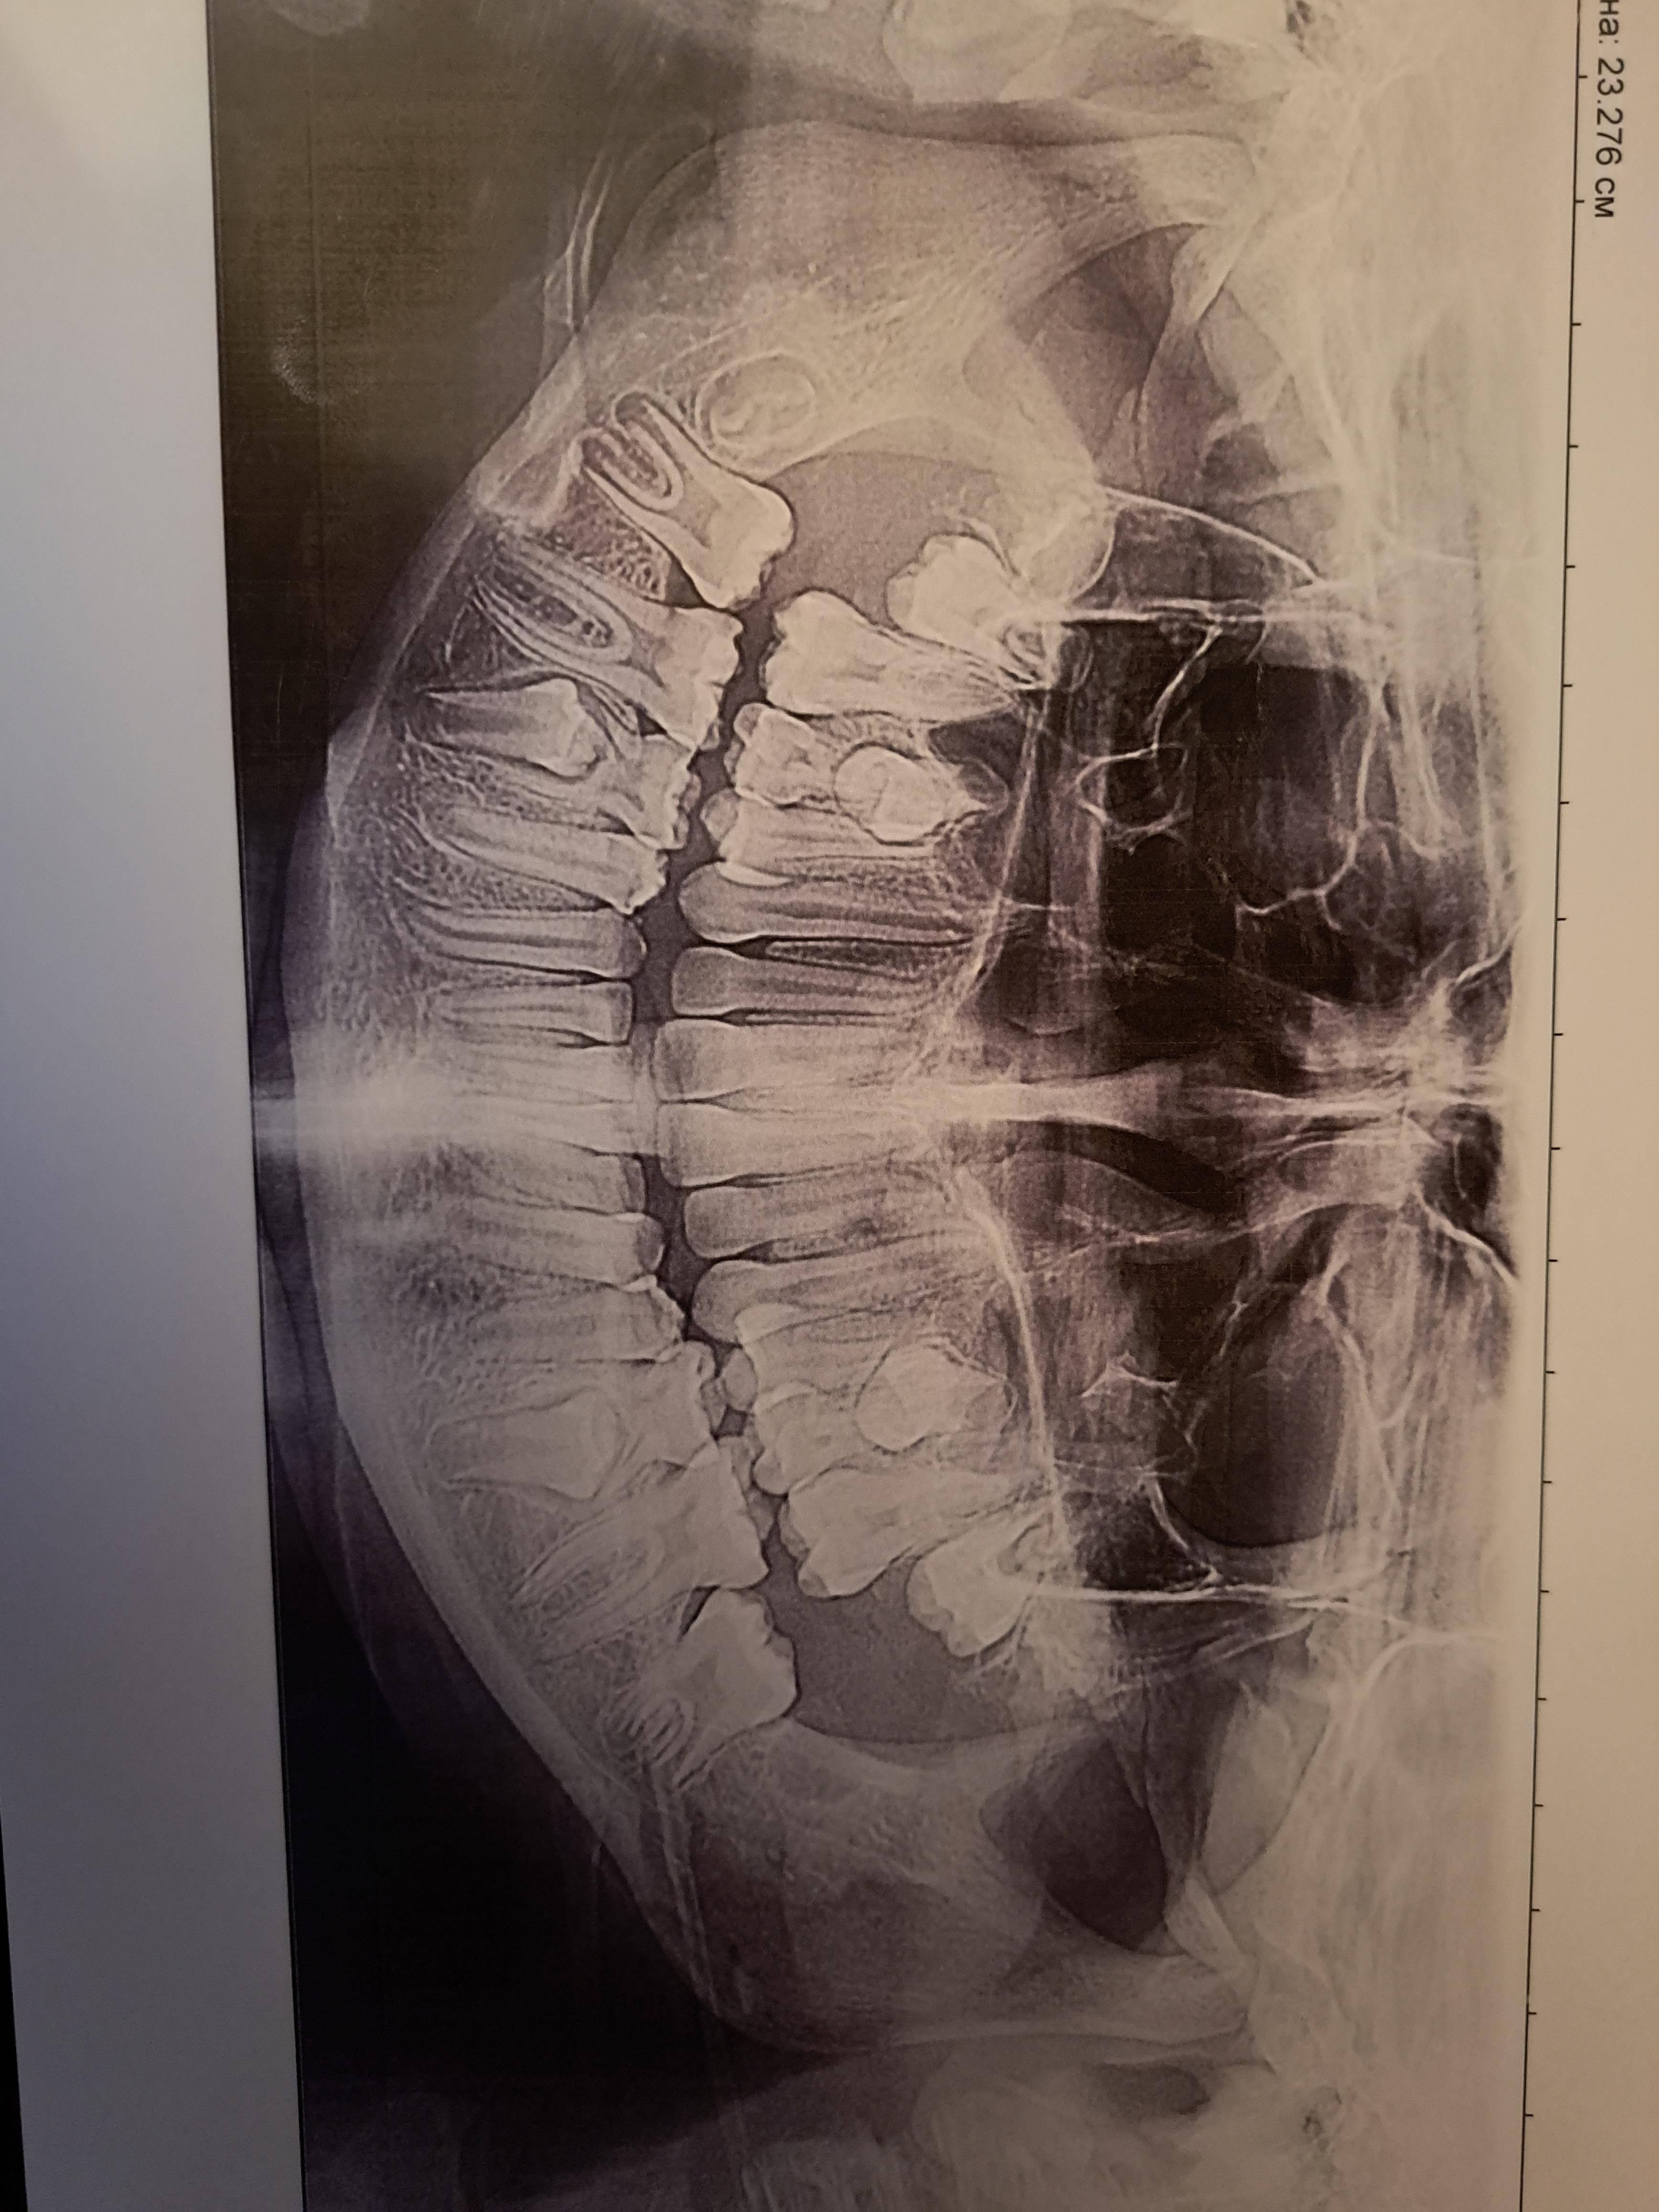

Здравствуйте, первый зуб у дочери выпал в 6.5 лет. Сейчас ей 12.5. Спросила у своего терапевта-стоматолога, надо ли выдергивать пятерки, она сказала сделать ОПТГ и показать ортодонту. Ортодонт неуверенно сказал, что лучше выдернуть, по 1 в две недели, начинать с нижних. Я слышала такую информацию, что если зубы не шатаются, при выдергивании можно повредить десну или зачаток зуба, лучше их самостоятельно пытаться расшатать, и ждать, когда выпадут сами. Навредить ребенку не хочется, но мой терапевт напугала, что если зубу расти некуда, он может вырасти внутри, и корень у молочного не рассосется. Как лучше все-таки поступить?